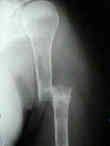

Se localiza, preferentemente, en los huesos donde existe médula ósea roja: vértebras, costillas, esternón, pelvis, cráneo y huesos largos (tercio proximal fémur y húmero).

Las fracturas patológicas de columna o fémur pueden ser el primer

síntoma. Se producen con un traumatismo mínimo o incluso sin trauma.

Radiográficos:

Las radiografías normales pueden mostrar osteopenia difusa.

"Lesiones perforadas" o en "sacabocado" sin ninguna formación de nuevo-hueso circundante. Su diámetro es variable (hasta 5 cm.), redondas y múltiples.

Con el tiempo las lesiones pueden cambiar de osteopenia difusa a más permeativa con patrón destructivo apolillado, y a veces con expansión cortical.

La destrucción del hueso ocurre con poca o ninguna formación de hueso reactivo a menos que haya una fractura patológica.

Los mielomas pueden presentarse como lesión solitaria o más normalmente como un tumor difuso, involucrando múltiples huesos, incluyendo vértebras, cráneo, pelvis y fémures.